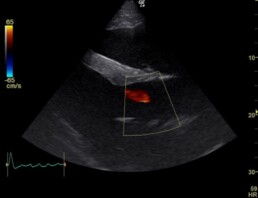

In der elektrokardiographischen und echokardiographischen Untersuchung zeigten sich die geringgradige Mitralklappeninsuffizienz (Schlussunfähigkeit der Herzklappe zwischen linkem Vorhof und linker Herzkammer), die geringgradige Trikuspidalkappeninsuffizienz (Herzklappe zwischen rechtem Vorhof und rechter Herzkammer), die geringgradige Aortenklappeninsuffizienz (Herzklappe zwischen linker Herzkammer und Aorta, Abb. 2) und das Vorhofflimmern (Herzarrhythmie) als unverändert. Die Herzdimensionsveränderungen liegen weiterhin vor, sind jedoch unverändert bis geringgradig verbessert (Abb. 1, 3).

Abb. 2: Aortenklappeninsuffizienz, sichtbar als rötliche Farbfahne (rechte kaudale lange Achse)